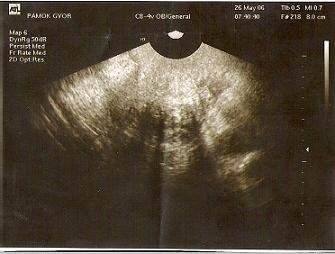

. Vasárnap tesztelsz? Mi vasárnap indulunk Balcsira, hát akkor majd pénteken elolvasom, mi az ábra! Én meg nem most, hanem következő hétfőre kaptam 18 h-ra időpontot uh-ra! Az már a 7. hét, akkor már tutira kell látsszon. Várom nagyon..